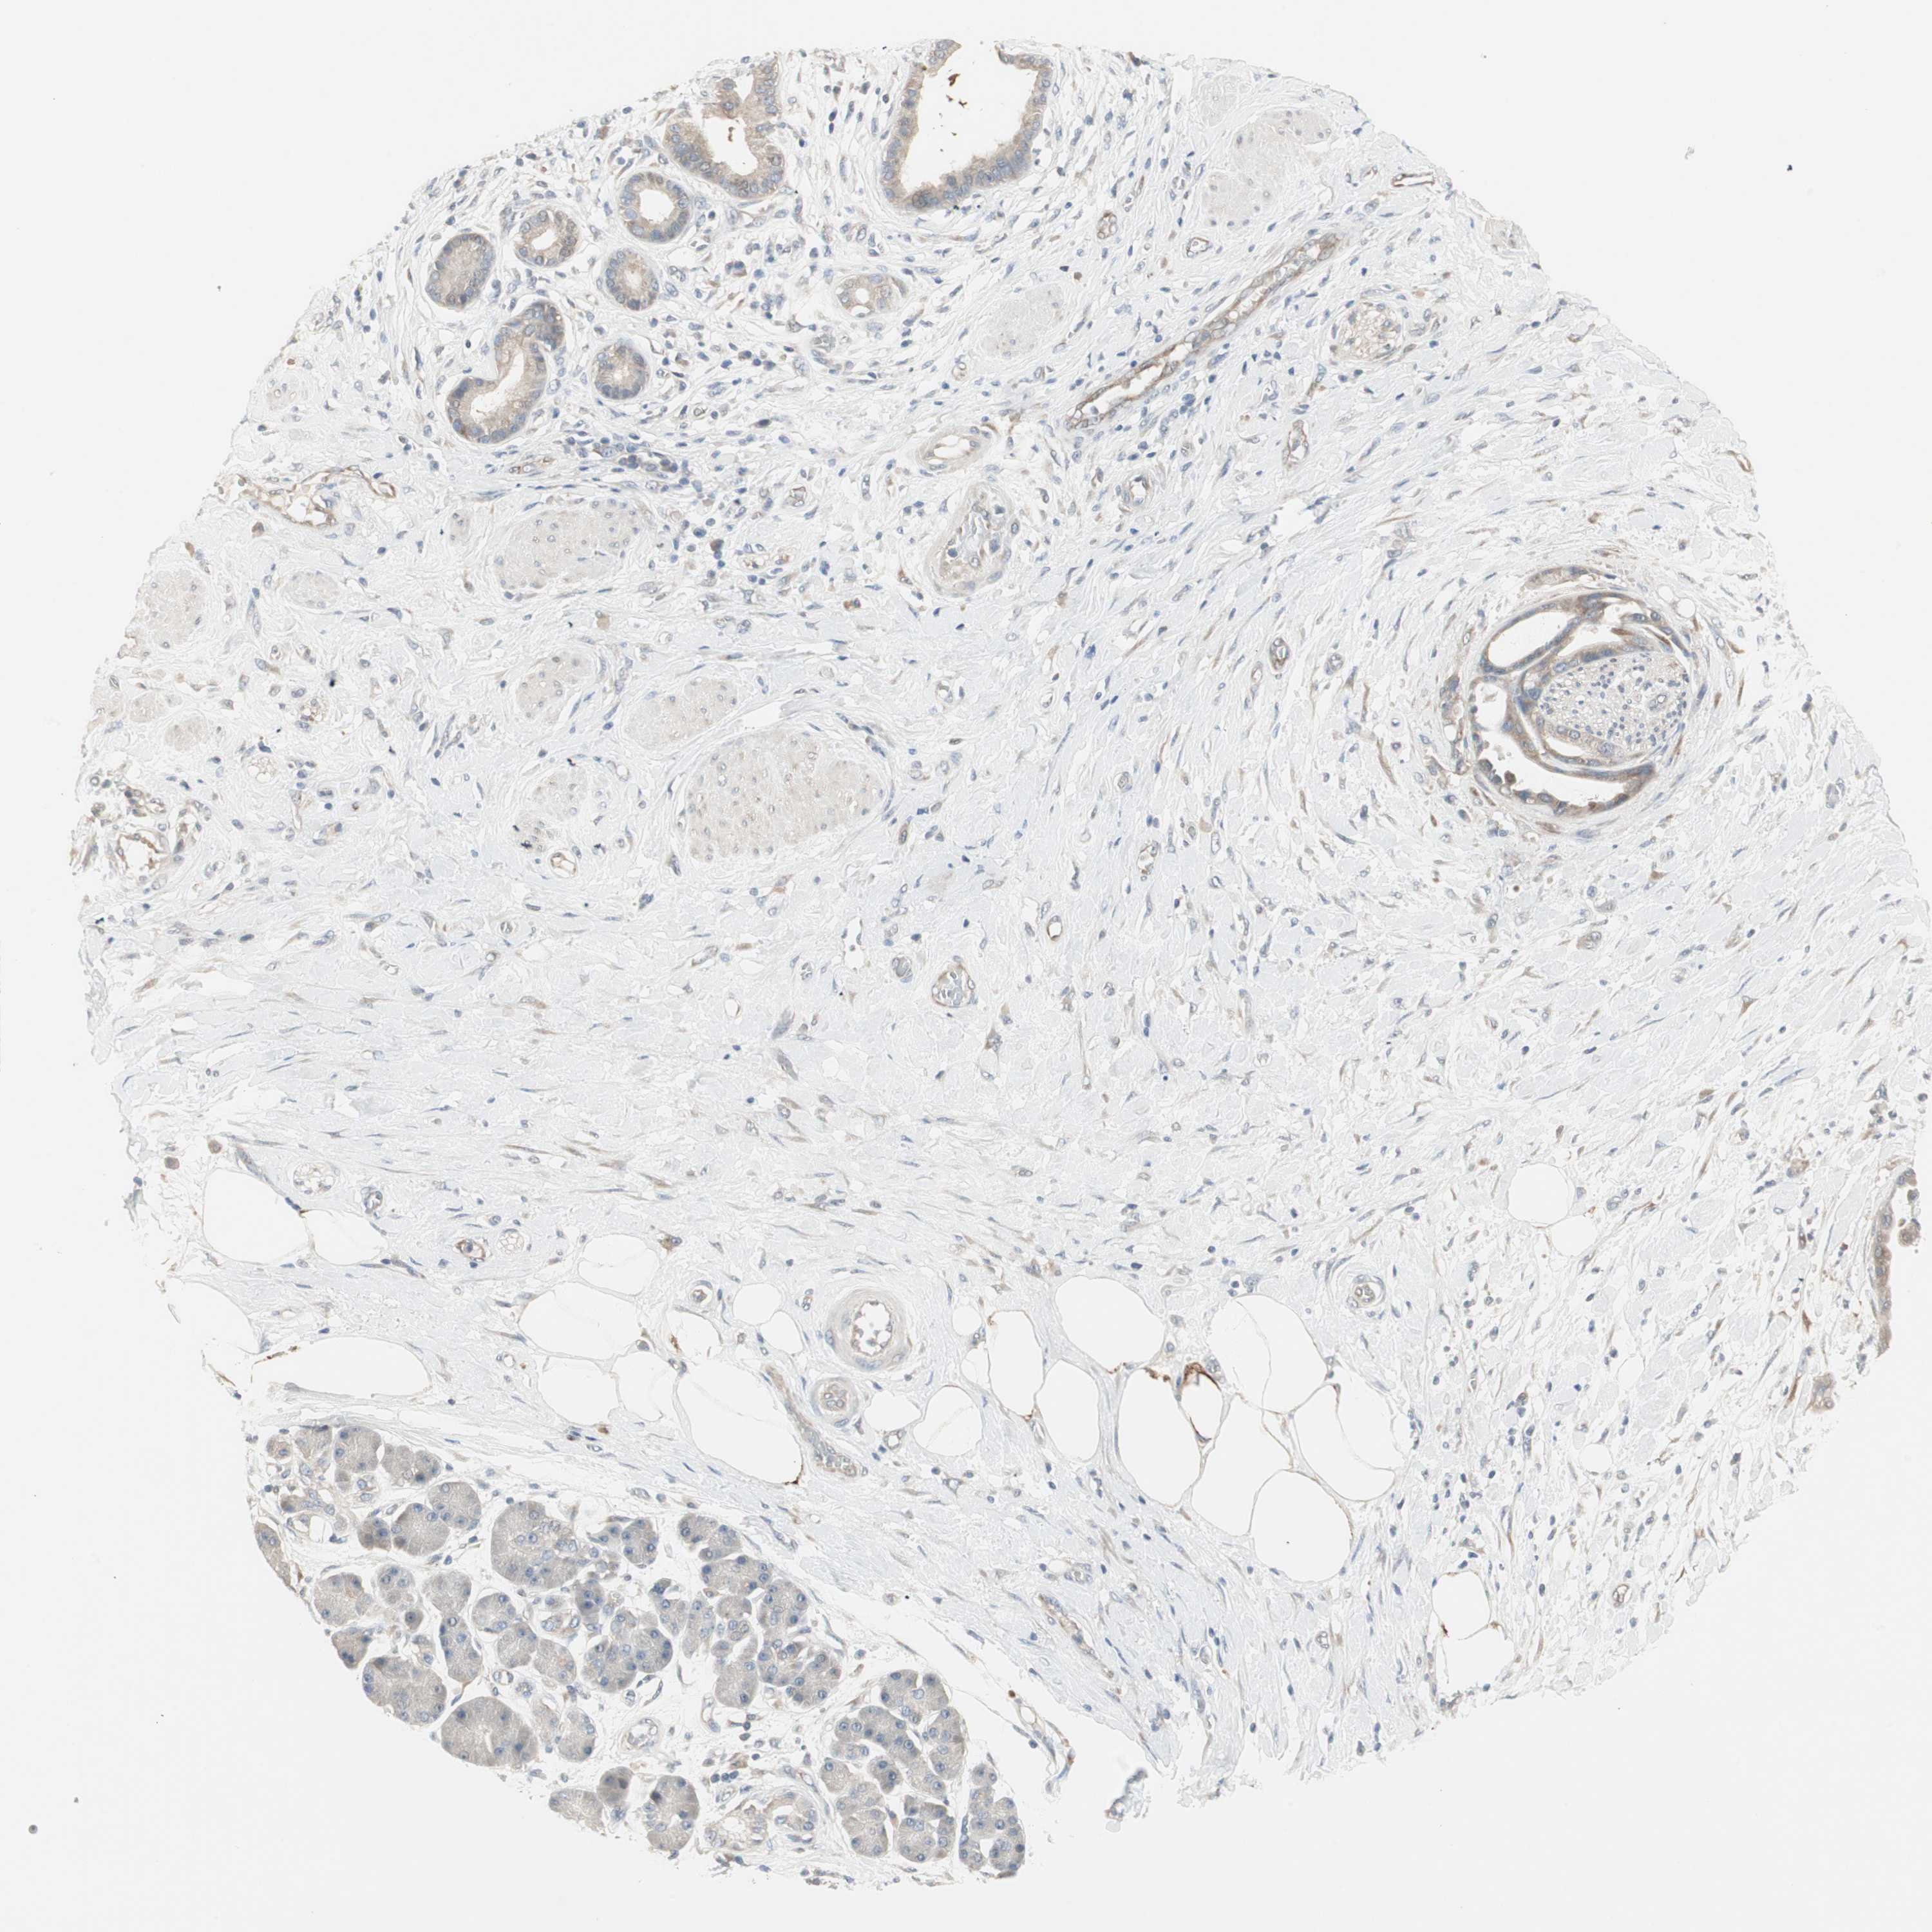

PANCREATIC CANCER - Protein expressioni

A mouse-over function shows sample information and annotation data. Click on an image to view it in a full screen mode. Samples can be filtered based on level of antibody staining by selecting one or several of the following categories: high, medium, low and not detected. The assay and annotation is described here.

Note that samples used for immunohistochemistry by the Human Protein Atlas do not correspond to samples in the TCGA dataset.

Antibody stainingi

Antibody staining in the annotated cell types in the current human tissue is reported as not detected, low, medium, or high, based on conventional immunohistochemistry profiling in selected tissues. This score is based on the combination of the staining intensity and fraction of stained cells.

Each image is clickable and will lead to virtual microscopy that enables deeper exploration of all samples and also displays staining intensity scores, fraction scores and subcellular localization as well as patient and tissue information for each sample.

Antibody HPA006009

Staining

High

Medium

Low

Not detected

Intensity

Strong

Moderate

Weak

Negative

Quantity

>75%

75%-25%

<25%

None

Location

Nuclear

Cytoplasmic/membranous

Cytoplasmic/membranous,nuclear

Adenocarcinoma, NOS

Adenocarcinoma, metastatic, NOS